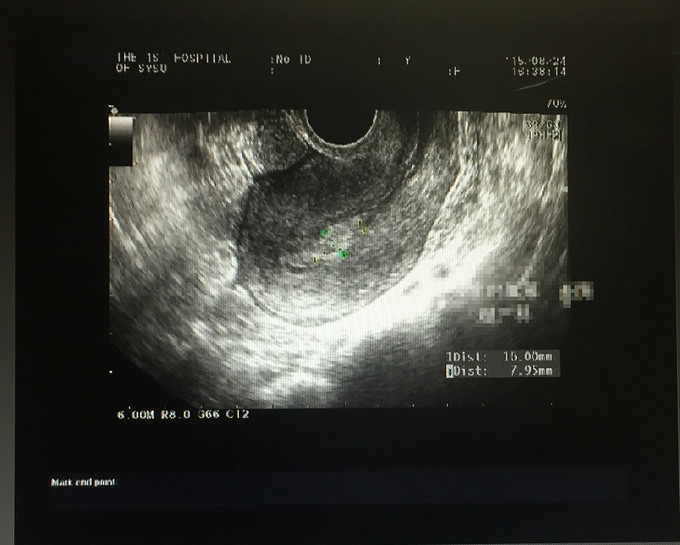

妇检:外阴:发育正常,阴毛分布正常;阴道:通畅,未见异常分泌物,粘膜正常无充血,水肿,无血污;宫颈:光滑,常大,无接触性出血,无抬举痛,未见活动性出血。宫体:前位,常大,无压痛。双附件:未扪及包块,无触痛。 外院输卵管造影:子宫形态,大小正常,右输卵管积液,左侧输卵管间质部梗阻。 我院B超:子宫内膜不均,考虑子宫内膜多发息肉。